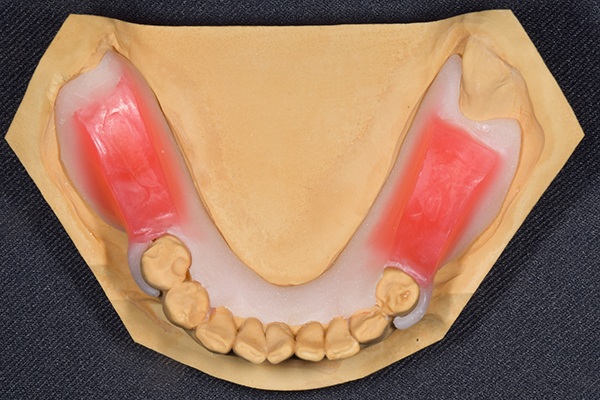

前歯が折れて当院にいらっしゃいました。 過去に下の入れ歯を作ったが、合わなくなってずっと入れ歯をいれていらっしゃらない患者様でした。 これは奥歯で噛むことができないため、前歯で噛むことを繰り返したために、負担に耐えられなくなった前歯が折れてかぶせ物ごと 外れてしまったのだと考えられます。 痛くない、違和感の少ない、下の入れ歯を作ることがこの方のゴールであると考えられました。

シリコンで精密な型取りを行いました。

噛み合わせチェックです。 奥歯でしっかりものが噛める様に高さを決めていきました。

金属を使用して、薄く違和感が少ない入れ歯が完成しました。 また、見た目にも気を使い、バネが見えにくい様な構造にしました。

義歯は下顎で、しっかり噛めること、違和感の少ないものという希望があったため、なるべく入れ歯を薄く作成するために金属をしようした義歯とした。

また、見た目もあまり義歯が目立たない様に、バネの部分を見えにくいように作成した。

下の入れ歯